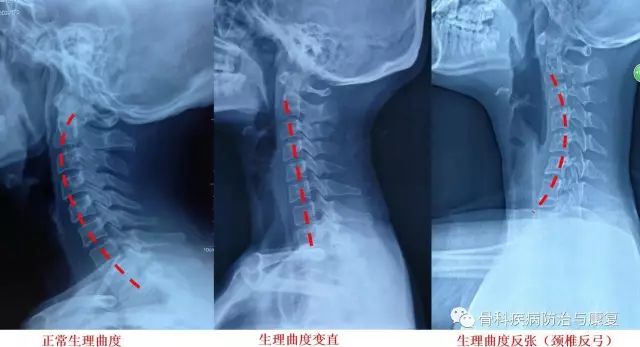

【颈椎|颈椎健康操:每天三分钟,告别颈肩痛】我国颈椎病近十年来发病率呈直线上升趋势 。 据不完全统计 , 全世界每天近一亿人发生颈肩臂痛 , 该症状群已成为骨科门诊最常见的问题 。 颈椎病的发生与不良生活习惯和生活环境有关 , 关键在于预防 , 颈椎病早期主要是颈椎曲度改变 , 生理曲度变小 , 逐渐出现僵直 , 最后呈现“反弓”改变 。

颈椎生理曲度不同改变X片表现